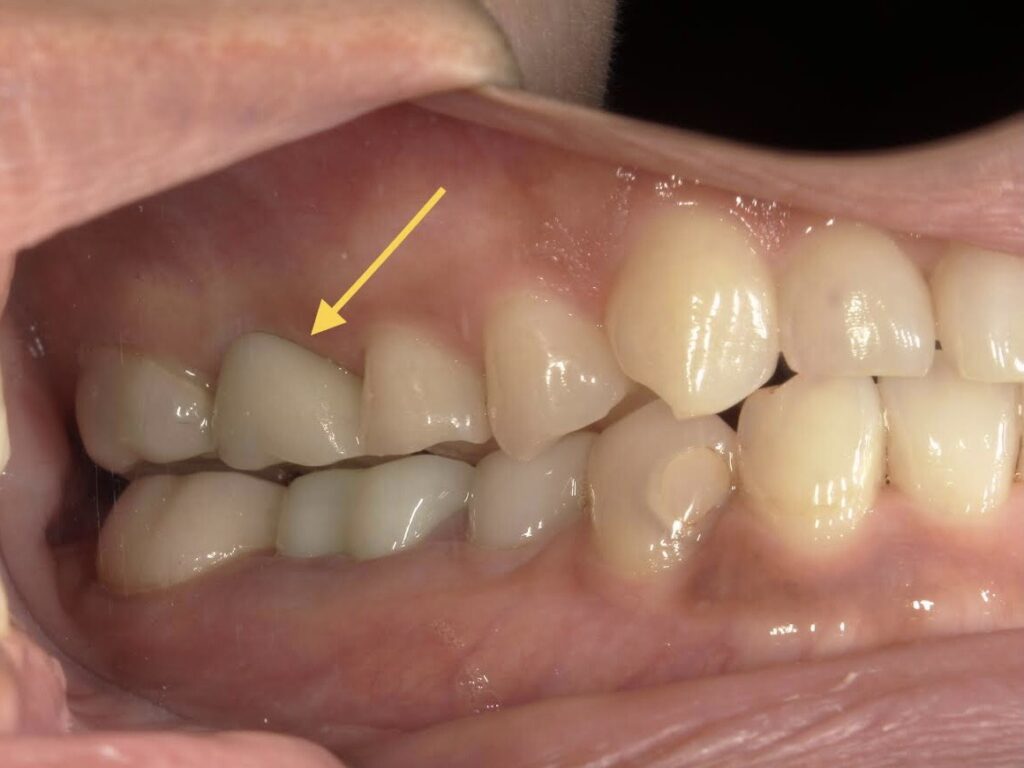

【A様】

側方面観(閉口)

年齢 | 30代後半 |

性別 | 女性 |

主訴 | 歯を抜いた後、周りの歯を削ることなく噛めるようにしたい |

施術内容 | 右上第一大臼歯欠損部にインプラントを埋入し、ジルコニアクラウンを被せてあります |

治療期間 | 約1年(抜歯からジルコニアクラウン装着まで) |